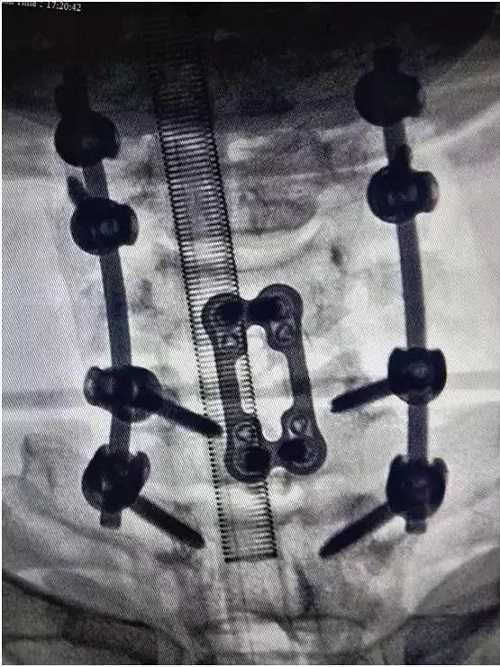

患者术后X光片

经过近10小时的努力,手术顺利完成,患者麻醉清醒后进食及精神状态良好。复查颈椎CT见颈椎骨折脱位完全复位,内固定位置及牢固程度令人满意,达到了复位、稳定、减压、脊髓损伤没有加重的目的。